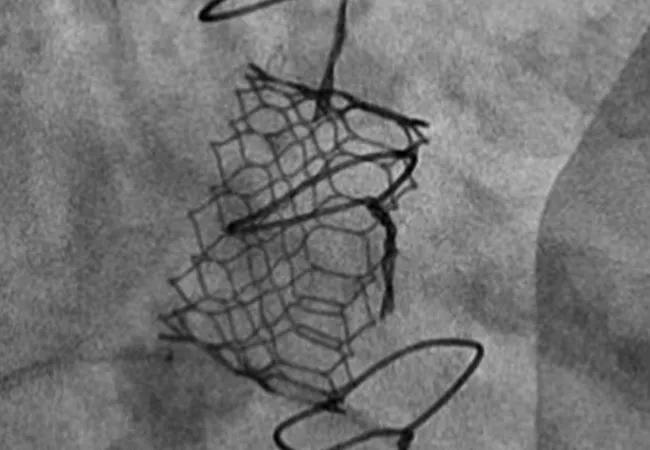

The “minimalist approach” to anesthesia and imaging guidance used in many transcatheter aortic valve replacement (TAVR) cases appears to be feasible and safe for use in valve-in-valve (ViV) transcatheter mitral valve replacement (TMVR) as well. So concludes a research letter from a Cleveland Clinic team published in JACC: Cardiovascular Interventions (2022;15[12]:1288-1290).

The minimalist approach involves use of either conscious sedation or monitored anesthesia care (MAC) in lieu of general anesthesia, with intracardiac echocardiography used in lieu of TEE. “This offers the advantages of minimized anesthetic requirements with expected reductions in patient recovery time and potential risks associated with endotracheal intubation and general anesthesia,” Dr. Krishnaswamy explains.

The researchers identified all patients (N = 56; mean age, 75 years) who underwent transfemoral-approach ViV TMVR at Cleveland Clinic from January 2012 through December 2020. Initial cases were all performed using general anesthesia, but after the group’s first three years of experience (2012-2014), operators could elect to perform the procedure with patients under either conscious sedation or MAC. Across all cases, transseptal puncture was guided either by intracardiac echo for patients receiving MAC/conscious sedation or by TEE for patients receiving general anesthesia.

Of the study’s 56 patients, 14 received general anesthesia and 42 received MAC or conscious sedation. There were no significant baseline differences between the two groups. Valve placement was successful in all cases, with no instances of paravalvular regurgitation and no mortalities at 30 days. Other 30-day clinical outcomes and longer-term outcomes were statistically comparable between the two groups, with one exception: mean hospital length of stay (LOS) was 50% shorter in the MAC/conscious sedation group (3 ± 3.4 days) than in the general anesthesia group (6 ± 6.2 days).

In response, Cleveland Clinic operators have begun to apply a method used to optimize hemodynamics in ViV TAVR — namely, high-pressure postdilation/surgical valve fracture — to ViV TMVR as well. Among the 45 cases from the current series undertaken after introduction of this adjunctive technique, 32 underwent high-pressure postdilation/surgical valve fracture, with surgical frames not undergoing fracture in just 11 cases. The decision not to fracture was driven by operator concern about limited space around the left ventricular outflow tract.